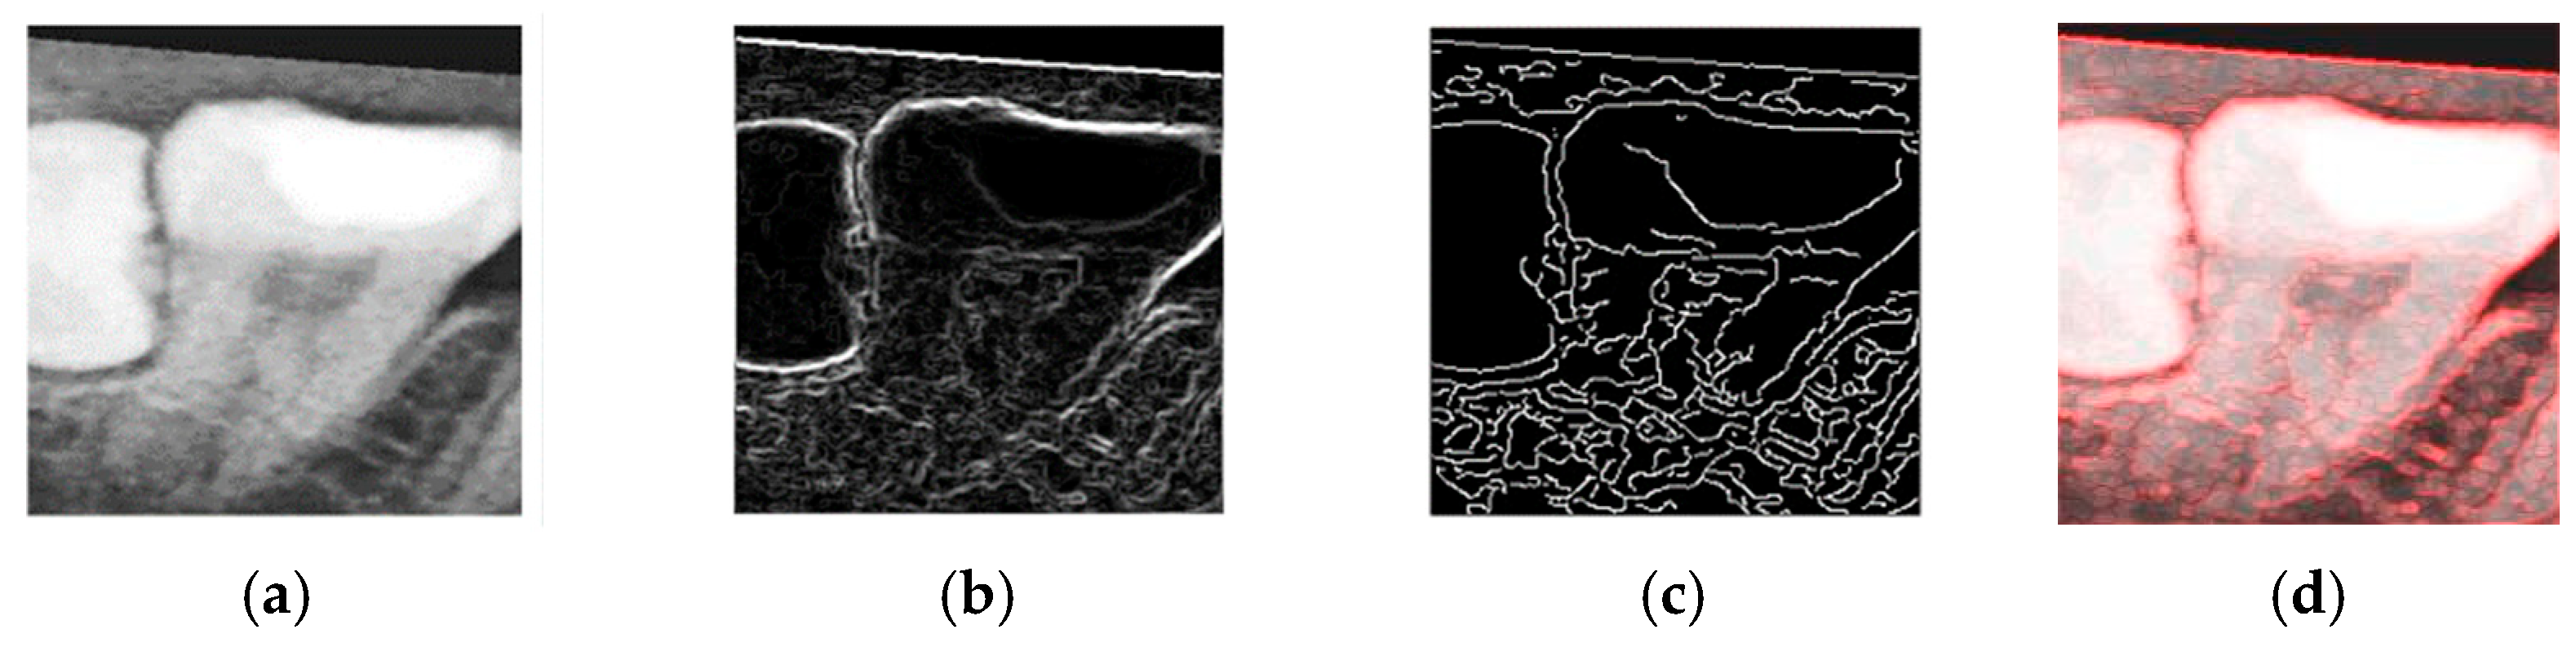

To determine the most effective enhancement method, this study compared the visual outcomes of Sobel and Canny edge detection, as shown in Figure 12a–c. Based on visual inspection, the images processed with Canny edge detection appeared blurrier and contained more noise compared to those enhanced using the Sobel method. Consequently, Sobel edge detection was selected as the preferred enhancement method. To further highlight the image features, this study applied a color-overlay approach by superimposing the Sobel edge map onto the original image, thereby enhancing structural visibility. The resulting enhanced image is shown in Figure 12d.

Figure 12. The results of image enhancement on a tooth image. (a) Original image. (b) The result of Sobel edge detection. (c) The result of Canny edge detection. (d) The final enhancement results.